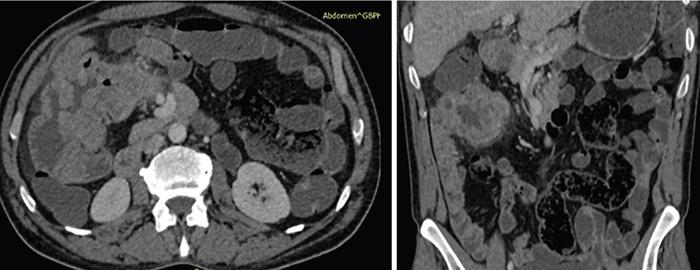

Computed tomography

CT enterography

CT enteroclysis